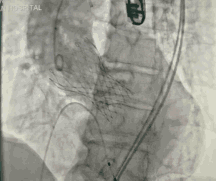

今天直播的这位患者是85岁的老年男性,10年前因主动脉瓣重度狭窄植入CoreValve 26mm瓣膜,是我国第一例TAVR患者,术后恢复情况良好。

6个月之前,患者出现反复胸闷气急,心超提示人工生物主动脉瓣置换术后,中重度主动脉瓣口反流,轻度瓣周漏。这例患者目前已85岁,同时合并持续性房颤、高血压、心功能不全Ⅲ级,STS评分7.56%,外科手术风险高危。

葛均波院士、周达新教授结构团队对这位生物瓣衰败的老年男性患者行瓣中瓣植入术,术中选择了23mm VenusA-Valve(杭州启明),植入过程顺利,术后冠脉无堵塞,未出现瓣周漏,术后跨瓣压差接近于0,赢得了参会专家的激烈掌声。

图3 TAVR瓣膜释放前造影